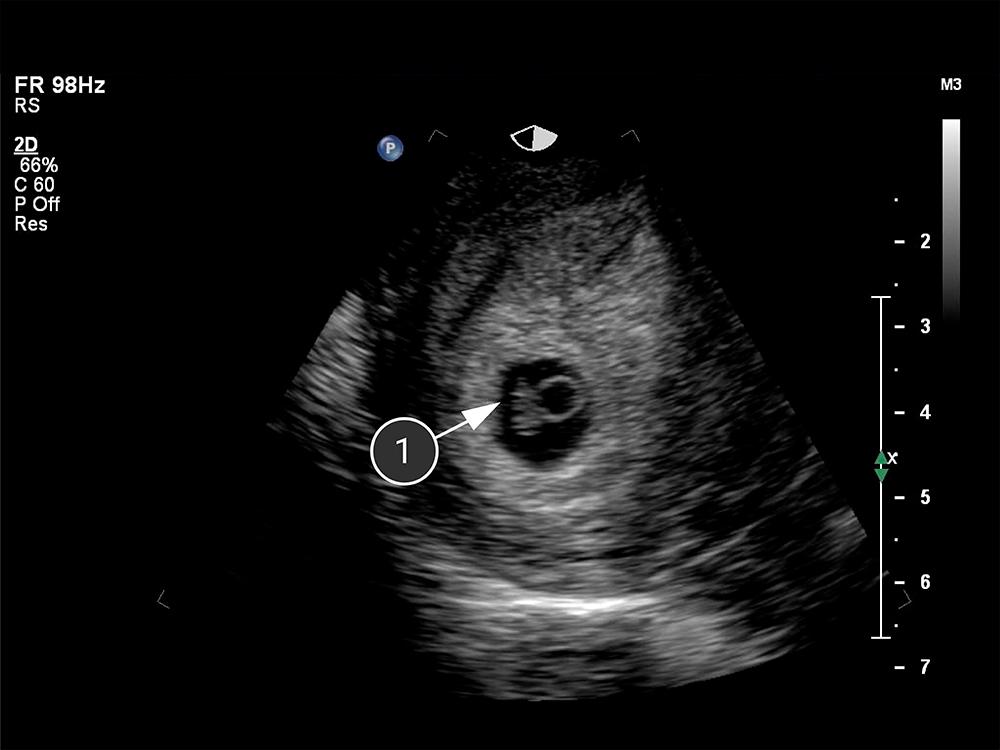

Lo que se puede ver en el ultrasonido

En esta etapa de desarrollo, el bebé se llama embrión y comprende aproximadamente 250 células. En la imagen, el pequeño punto blanco es la formación del embrión dentro del óvulo fetal.

embrión